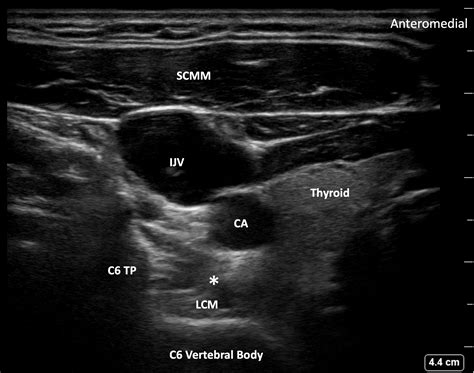

The stellate ganglion is a critical component of the sympathetic nervous system, which plays a crucial role in regulating various bodily functions such as heart rate, blood pressure, and sweating. Located in the neck, it is formed by the fusion of the inferior cervical and first thoracic ganglia. The stellate ganglion is a key player in the body’s “fight or flight” response, making it a target for interventions aimed at managing conditions related to stress and pain.

The Stellate Ganglion Block procedure is typically performed under fluoroscopic guidance to ensure precise placement of the anesthetic. Here is a step-by-step overview of what patients can expect:

1. The patient is positioned lying down on their back with their head slightly turned to the side.

2. The skin over the injection site is cleaned and numbed with a local anesthetic.

3. Using fluoroscopy, the physician guides a needle to the stellate ganglion.

4. A small amount of contrast dye is injected to confirm the correct position of the needle.

5. The anesthetic is then injected into the stellate ganglion.

6. The patient is monitored for a short period to ensure there are no immediate complications.